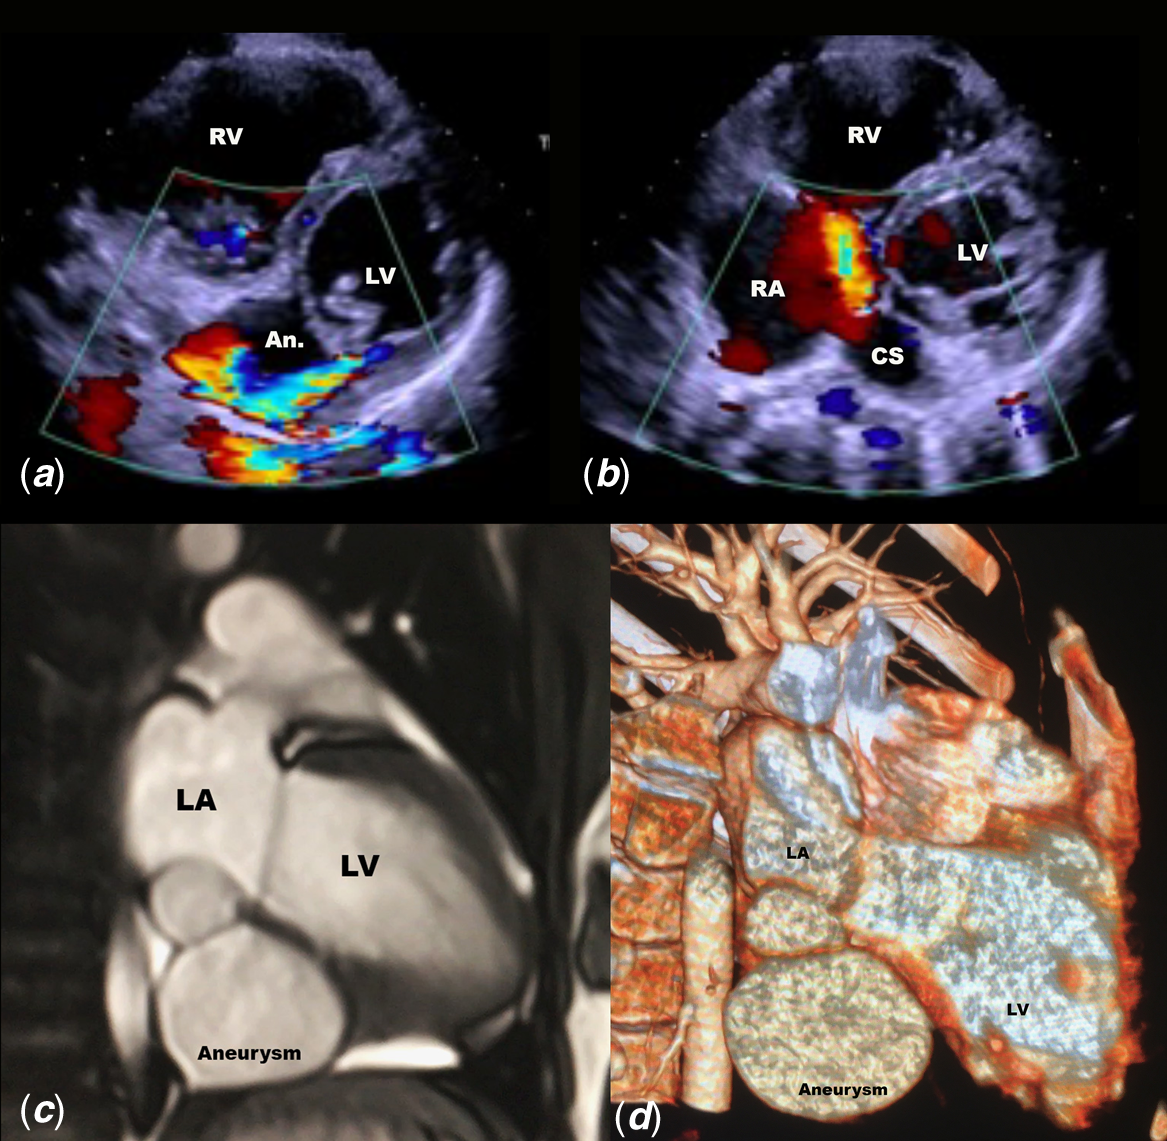

A 2-week-old newborn was referred for cardiac evaluation because she had a systolic murmur since the first day of life. The first echocardiography suspected an abnormal pulmonary venous return in coronary sinus. Her parents reported no family history of CHD. On physical examination, she was eupneic with normal oxygen saturation. The electrocardiogram showed a sinus rhythm, with normal P waves’ morphology. Echocardiogram revealed a bulky outpouching of the left ventricle (LV) located behind the mural leaflet of the mitral valve. Colour Doppler showed multiple small orifices between the LV and the outpouching with a maximal Doppler velocity of the jet of 3 m/seconds. This aneurysmal structure went along the posterior wall of the left ventricle and communicated through a tiny orifice with the right atrium via the coronary sinus (see Fig 1a and b). Doppler interrogation of this unusual flow showed a continuous flow at a velocity of 2 m/seconds. The systolic pulmonary arterial pressure was moderately elevated at 40 mmHg. Coronary sinus was mildly dilated and pulmonary veins were normally connected to the left atrium. A large ostium secundum atrial septal defect was also observed. This combination of the shunt through the submitral aneurysm and the right heart via the coronary sinus and the interatrial shunt resulted in a moderate diastolic overload of the right ventricle. At that time, the patient was not eligible for invasive procedure or surgery considering her low weight of 2.5 kg. Follow-up until the left-to-right shunt would be significant was decided, but patient who lived oversea was lost to follow-up.

Figure 1. (a ) High velocity shunt between the LV and the submitral aneurysm behind the posterior leaflet of the mitral valve. ( b ) Dilated coronary sinus with large orifice in the right atrium and colour Doppler flow from the submitral aneurysm. ( c ) 2D-CT showing the biloculated submitral aneurysm below the left ventricle and the left atrium (see also supplementary files). ( d ) 3D-CT showing the location of the submitral aneurysm.

CT scan is shown in Figure 1. The submitral aneurysm measured 5 cm, and the defect between the LV and the outpouching was a narrow 7-mm channel. The wall of the aneurysm was thin and not muscular. In order to further assess the relationship with adjacent structures, right and left heart catheterisations were performed. Angiogram of the coronary arteries was normal and showed no fistula between the submitral aneurysm and coronary arteries. The left ventriculography evidenced the shunt between the left ventricle and the biloculated cavity (Fig 2). The communication between the submitral aneurysm and the coronary sinus was narrow.